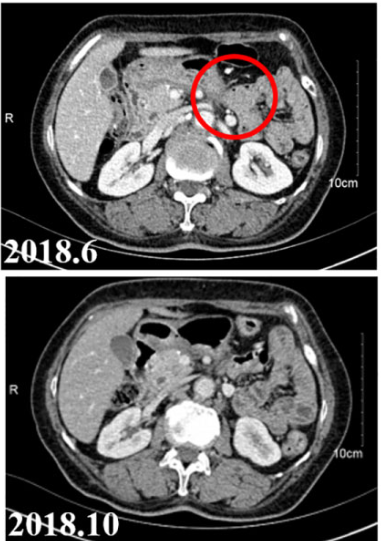

9月18日,Geneos Therapeutics宣布其研发的个性化癌症免疫疗法取得了重大突破,两名接受治疗的侵袭性癌症患者已分别持续治疗超过六年和五年,两位患者均实现完全缓解,未发生严重不良事件,目前均保持无复发健康状态。